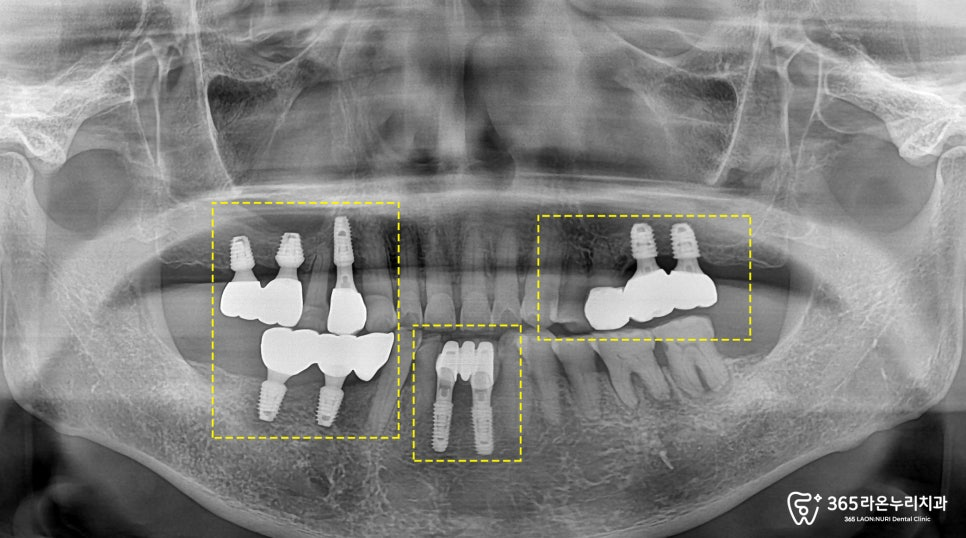

그리고 나서, 실제 구강과

엑스레이 촬영을 통해

치아의 건강 상태를

확인하게 됩니다.

왼쪽 아래 앞니가 하나 결손되어 있는 것이

먼저 관찰되며, 다른 치아들도

흔들리고 상태가 좋지 않았습니다.

특히, 결손된 앞니 부위의

골도 심하게 내려가 있었습니다.

위턱 양쪽의 어금니가 모두 사라졌고,

오른쪽의 경우 작은 어금니 하나가

없는 모습입니다.

반대편에 있는 작은 어금니 하나도 심하게

파절되어, 코어 + 크라운을

진행해드리기로 결정했습니다.

아래턱 역시도, 치조골이 많이

내려가게 되면서 치아 뿌리쪽이

많이 드러나고 있었습니다.

엑스레이를 보시면 전체적으로

치아 뿌리가 드러날 정도의

골소실이 일어나 있는 것을

더욱 명확하게 확인할 수 있었는데요.

보시는 것과 같이

잇몸뼈가 뿌리 끝까지 녹아

더이상 치아를 지지하지

못하고 흔들리고 있었는데요.

이처럼 전체적으로 치아의 상태가 좋지

않았던 곳들은 발치 후 임플란트 식립 및

뼈이식 치료를 진행하기로 결정하게 되었습니다.